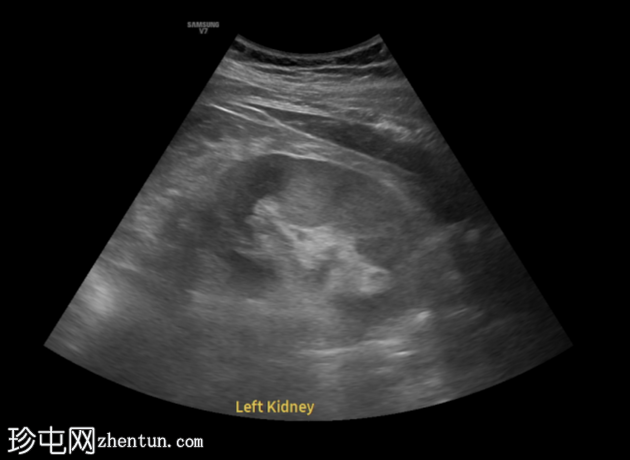

左侧腰痛伴血尿。

年龄:45岁

性别:男

超声

检查

超声显示左侧轻度肾积水,由膀胱输尿管连接处一枚7毫米的远端输尿管结石阻塞所致,输尿管射流正常。

肾积水并非总是由输尿管结石引起。肾盂和肾盏扩张的程度与结石大小并不一定相关。

较小的结石有时可导致中度上游扩张,而较大的结石可能仅引起轻微的充盈感,这取决于患者的引流和水合状态。